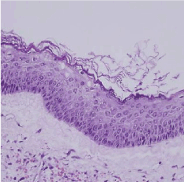

Figure 5. Keratocyst-Prominent stratified epithelium with orthokeratosis.